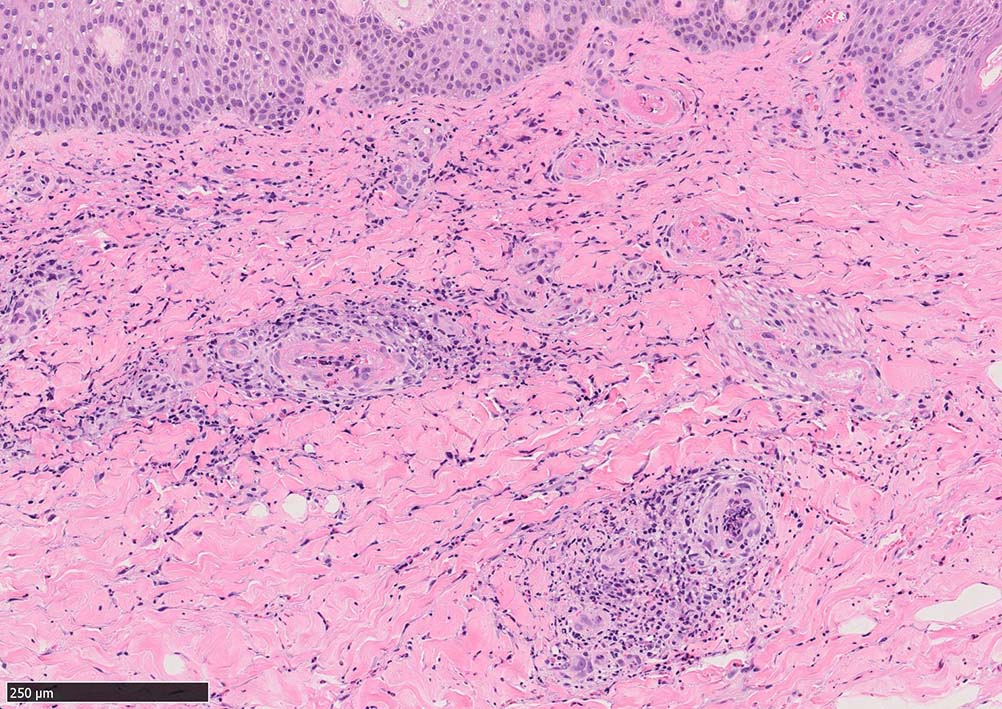

IWT-case03 マダニに咬まれた. 自分で虫体を除去したが傷がびらん化し, 発熱を来したため, 来院する.

痂皮の下に硝子様凝固物があり, 周囲には壊死組織が形成されている. 近傍の細血管には凝固物による閉塞の所見があるように見える. 連続する細血管には, fibrinoid necrosisを呈する壊死性血管炎が認められる.